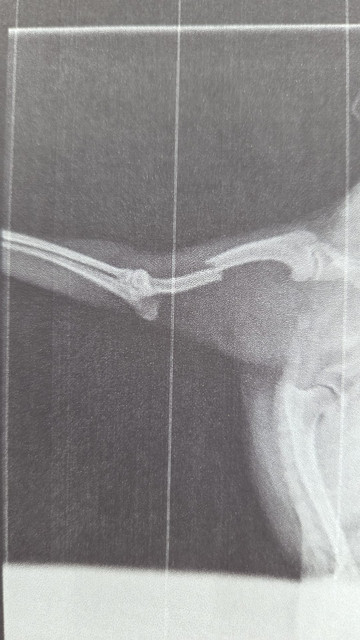

Unser kleiner Yoko, ein junger Yorki- Mischling (geb. 2024), hat sich beim Spielen mit seinen Hundefreunden schwer verletzt. Am vergangenen Mittwoch brach er sich beim Toben im Auslauf überraschend den linken Vorderlauf – ein schmerzhafter und dramatischer Moment für alle Beteiligten.

Unsere Kollegin eilte sofort zu ihm und umgehend brachten wir ihn hier zum Tierarzt. Dort stellten die Ärzte nach dem Röntgen einen Bruch von Radius und Ulna fest. Die Verletzung war so schwer, dass eine spezialisierte Operation in einer Tierklinik nötig wurde.

Bereits am Freitagmorgen fuhr Yoko in die Klinik – und am Nachmittag konnten wir ihn zum Glück wieder in die Arme schließen. Die Operation war erfolgreich: Eine Osteosynthese mit einer 2mm Knochenplatte war notwendig.

Doch damit ist es nicht getan – in der nächsten Zeit benötigt er Schmerzmittel, strikte Leinenruhe, Physiotherapie und einige Zeit später eine zweite OP, um die Platte wieder zu entfernen.

Die geschätzten Gesamtkosten: ca. 4.000 €